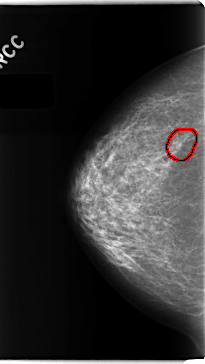

C_0151_1.RIGHT_CC

RIGHT_CC LINES 4728 PIXELS_PER_LINE 2664 BITS_PER_PIXEL 12 RESOLUTION 50 OVERLAY

FILE: C_0151_1.RIGHT_CC.OVERLAY

TOTAL_ABNORMALITIES 1

ABNORMALITY 1

LESION_TYPE CALCIFICATION TYPE PLEOMORPHIC DISTRIBUTION CLUSTERED

ASSESSMENT 4

SUBTLETY 3

PATHOLOGY MALIGNANT

TOTAL_OUTLINES 1

BOUNDARY